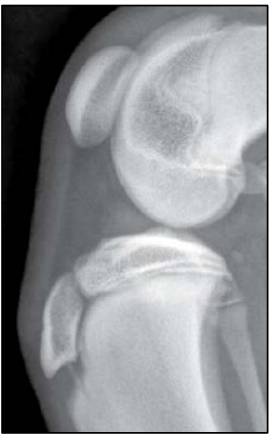

Observe a imagem a seguir.

Thrall, 2014.

A imagem acima representa uma radiografia em projeção mediolateral do joelho de um Labrador de 5 meses de idade. De acordo com a interpretação da imagem, as fises ósseas abertas podem indicar que